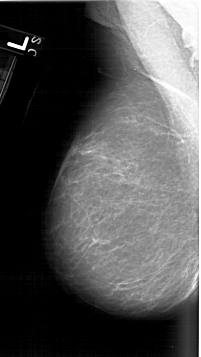

A_1610_1.RIGHT_CC

RIGHT_MLO LINES 6166 PIXELS_PER_LINE 3361 BITS_PER_PIXEL 12 RESOLUTION 43.5 OVERLAY